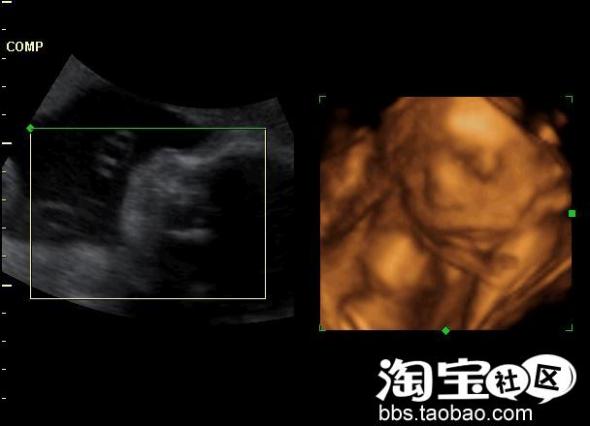

我相信了,结果我的防备心理完全解除,电脑想上就上,这段时间持续了8个月。这期间,有很多人叫我不要用电脑,说对宝宝不好,我一直是半信半疑,也开始有了担心,所以我在6个月的时候做了四维彩超

我见到了宝宝在我肚子里的样子,看见宝宝蛮健康的,没有检查出畸形, 我忐忑的心放下了不少。可在临产前两个月,不安和紧张的心理又出现了,想想即使是四维彩超,尽管能发现绝大部分胎儿畸形,但受胎儿胎龄,姿势,羊水,活动等诸多因素影响以致部分器官与部分超声无法显示或显示不清,因此,诊断胎儿畸形符合率不可能100%。我想我会不会得了产前忧郁症呢!呵呵!!即使我现在控制上网时间、穿好防辐射YY会不会也晚了呢?